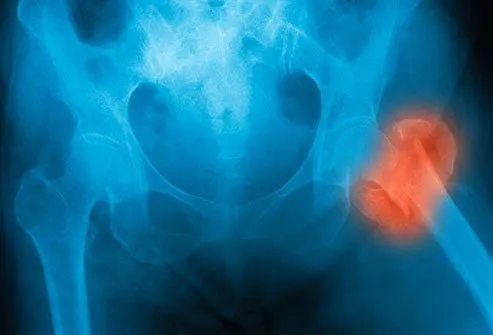

از دست دادن استخوان

افراد مبتلا به فشار خون بالا اغلب کلسیم بیشتری از طریق ادرار خود دفع می کنند. فشار خون بالا می تواند باعث شود بدن شما این ماده معدنی را که برای داشتن استخوان های قوی بسیار مهم است، سریع تر دفع کند. این امر می تواند منجر به شکستگی یا پوکی استخوان شود، به خصوص در زنان مسن.